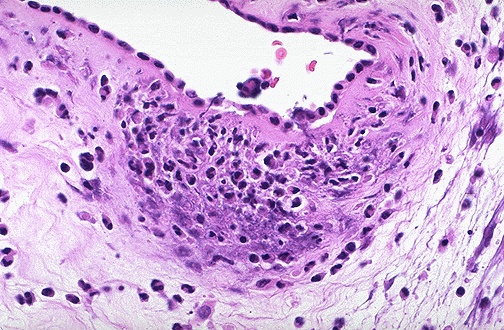

| Premature and/or prolonged rupture of fetal membranes (PROM) increases the risk for intrauterine infection, because bacteria can pass into the normally sealed amniotic cavity. This leads to acute inflammation as seen here as an acute chorioamnionitis within the fetal membranes. The fetus may become infected and suffer intrauterine fetal demise. Also, the inflammation may lead to premature labor and premature birth. |